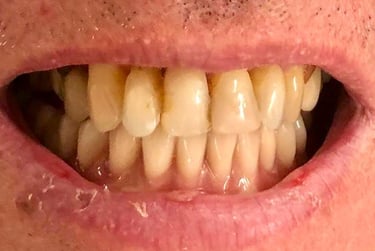

Aspecto Clínico Inicial - Fotografias originais — nenhuma contém retoques

Antes